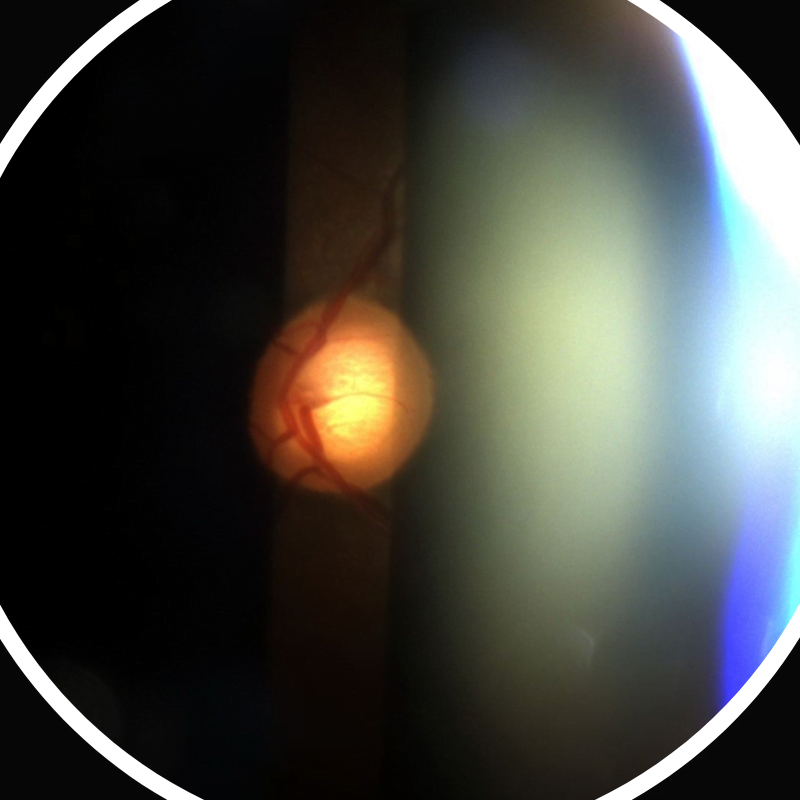

Steroid induced Glaucoma

It is the type of glaucoma that occurs secondary to long term steroid intake (Topical, inhalational, oral, or any other route) There are basically two terms under this umbrella of secondary glaucoma. Steroid induced ocular hypertension It is the condition where steroid intake has caused the intraocular pressure or the eye pressure to increase. But …